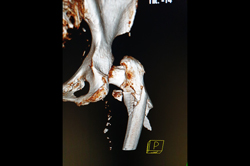

Neck Femur Fracture